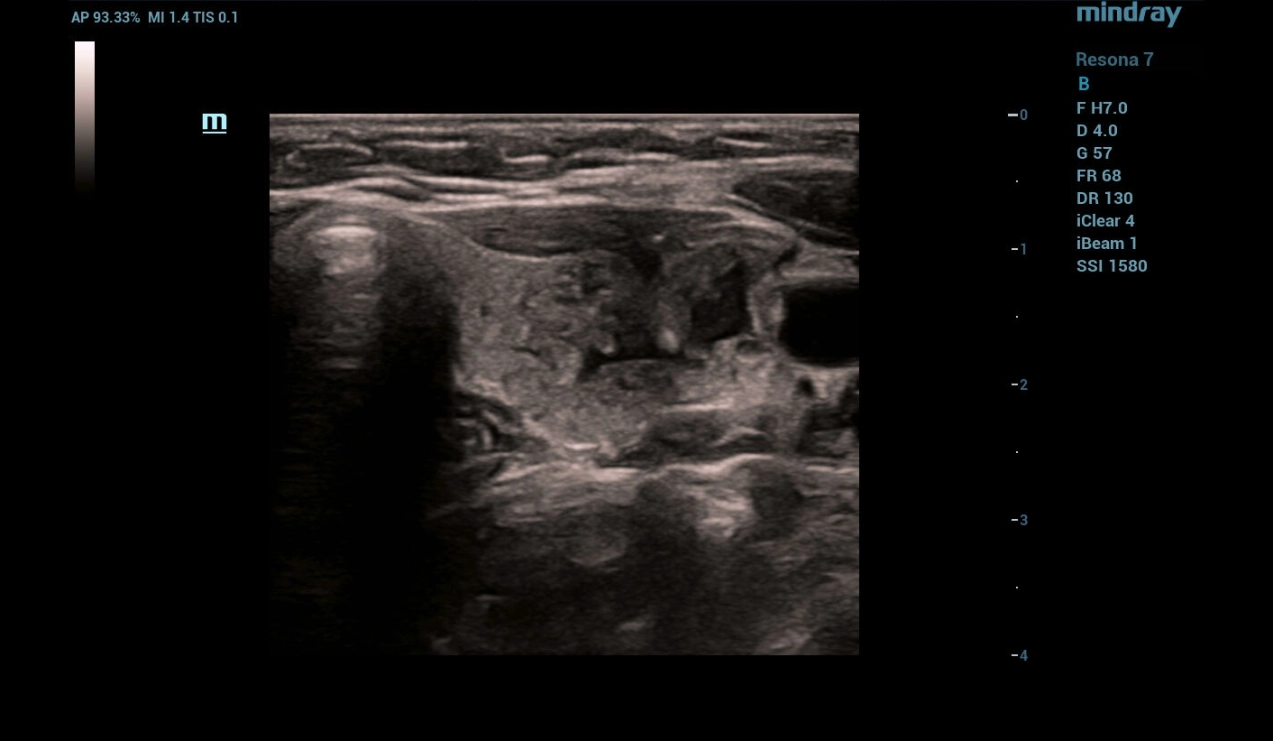

As the necessary exposure was completed, the sclerosant was evacuated followed by completion of the manipulation and control ultrasound. In - mode a heterogeneous focal formation of the thyroid gland with absence of cystic component was detected (Fig. 8). CFD mode determines absence of blood flow in the focal mass with preserved perinodular vessels (Fig. 9). Strain elastography reveals elastographic heterogeneity of the focal mass with predominance of a soft tissue component (Fig. 10).

throid-sclerotherapy-fig8-pc

Figure 8. Control ultrasound of the thyroid after completion of sclerotherapy

Multiparametric ultrasound examination of the thyroid revealed a cystic focal mass in the left lobe without signs of malignancy.

Complete evacuation of the cyst contents was performed under ultrasound navigation with the injection of 2.0 ml of sclerosant with the exposure of 4 minutes and its subsequent removal from the cyst cavity. On control examination, complete recession of the cystic neoplasm walls was determined.